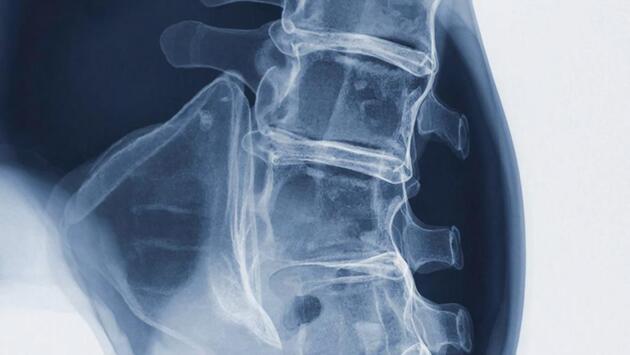

Сферические кластеры (сфероиды) смешивали с β-трикальцийфосфатом. Затем эту смесь транспортировали к позвонкам L4 и L5 у крыс с переломами позвоночника. Причиной же переломов стал остеопороз.